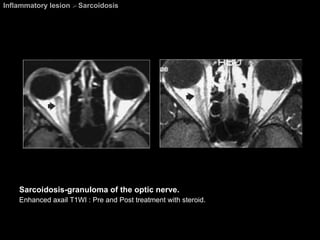

Sarcoidosis A granulomatous systemic disease. Pathology = Noncaseating granulomas  Diagnosis based on biosy. Affecting all races, both sexes, and all ages.  Presentation : asymptomatic with abnormal findings on CXR.   Visual system abnormalities  are the most common extrathoracic manifestations of sarcoidosis.

Sarcoidosis Ophthalmic lesions develop in approximately 25% of patients. Chest abnormalities are found in about 80% of patients with ocular sarcoidosis. Any part of the globe or orbit may be involved.  M/c orbital involvement  =  chronic dacryoadenitis .  May be unilateral and easily mimic a lacrimal gland tumor.

Sarcoidosis A Mikulicz-like syndrome  =  Sacoidosis involvement of bilateral lacrimal glands and salivary gland causings dry eyes and xerostomia. The most common cranial nerves to be affected are the  CN 2 , 7, 5, 8, 3, 6 respectively.

Inflammatory lesion  >  Sarcoidosis Sarcoidosis-granuloma of the optic nerve. Enhanced axail T1WI : Pre and Post treatment with steroid.